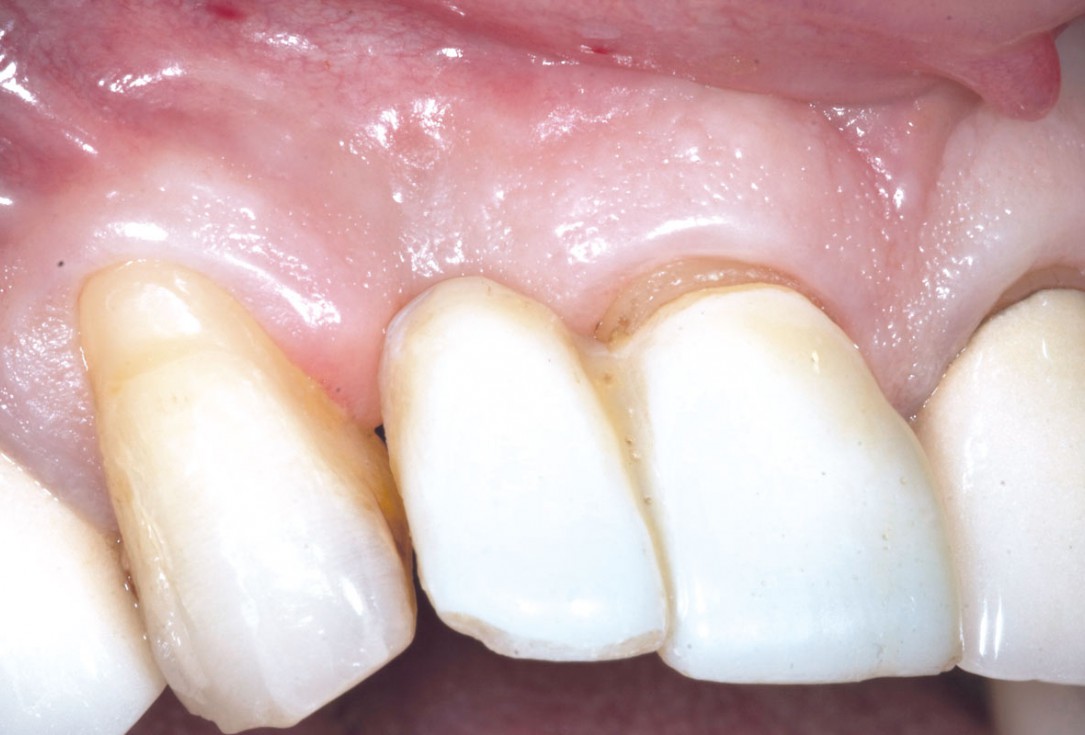

4/19 - Site after extractionBone augementation with maxresorb® - Dr. R. Cutts